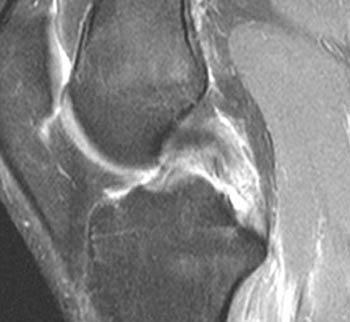

Mri web clinic — may 2015. PCL Tear - Radsource

PCL Tear - Radsource from radsource.us